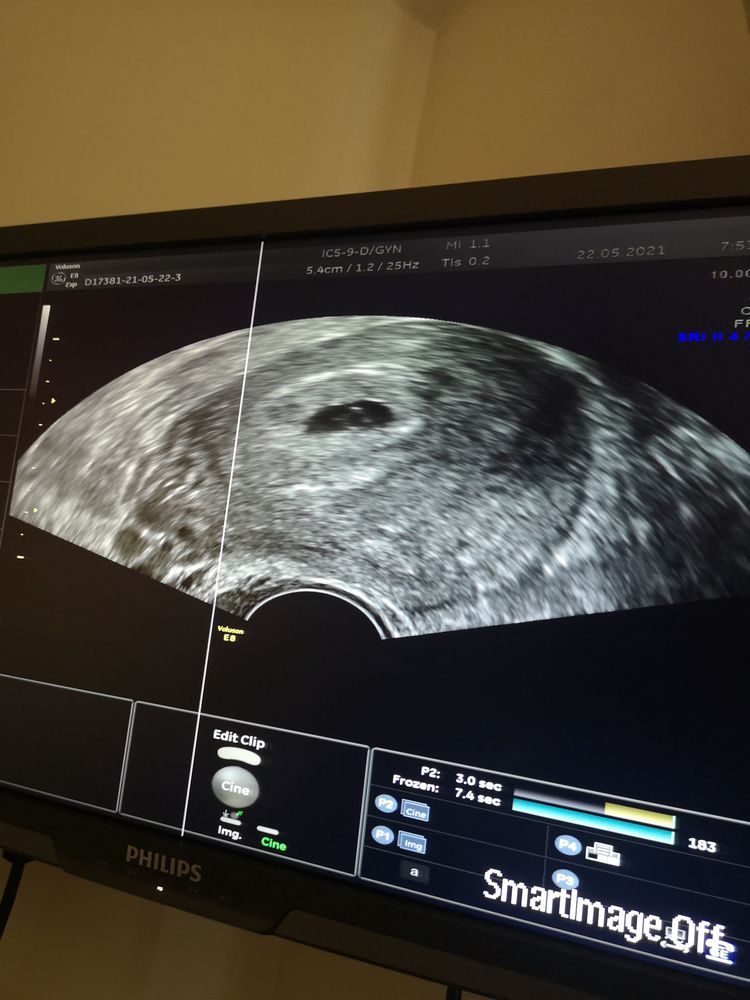

Моё узи 😍

Сегодня сходила на узи наконец-то, по месячным срок 6 недель и 3 дня, а по размерам эмбрион сказали где-то на 5,3 недели (овуляция была поздняя, где-то на 18 ДЦ) ,эмбрион 2,5 мм, желточный мешочек 2,5 мм тоже, сердцебиение 117 ударов, уже бьётся сердечко😍Беременность из левого яичника, хотя он "спал" почти полгода и тут вдруг овуляция в нем)